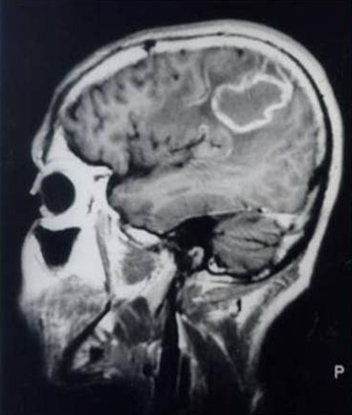

MRI brain in a patient with AIDS and reactivation of Chagas disease in CNS

Grupo de Estudos em Doenca de Chagas (GEDoCH), Departamento de Clínica Médica, Faculdade de Ciências Médicas, Universidade Estadual de Campinas, Sao Paulo, Brazil; used with permission